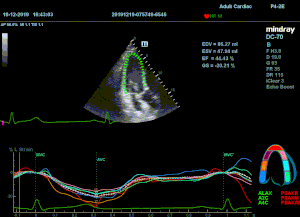

Всё изменилось с появлением технологии Speckle-tracking. Ультразвуковые приборы компании Mindray DC 8, 70, 80, Resona 6,7 оснащены данной функцией. Для использования необходим ЭКГ-канал. В чем же смысл данного технологического новшества? Прибор использует видео петли сечений миокарда, разбивает миокард на точки со стабильной визуализацией – speckle, и затем производит слежение каждой точки в течении нескольких сердечных циклов. Изменение пространства между точками дает нам представление о возможностях деформации миокарда, как продольной – Longitudinal Strain, так и деформации скручивания – торсии и Radial Strain.

Как работать с данным методом? Для Longitudinal Strain необходимо записать видео петли апикальных сечений в память прибора: 4С, 3С, 2С. Для повышения качества трекинга рекомендуется производить запись на выдохе пациента. Затем произвести разметку по линии эпикарда, перикарда и центра миокарда. Нажатием кнопки «начать слежение» активируется программный алгоритм, видео петля оживает вместе с размеченными точками-speckle’ами. При необходимости производится коррекция. После анализа всех трех сечений можно получить данных продольной деформации как в среднем значении, так и по каждому сегменту миокарда левого желудочка. Нормальным показателем считается Longitudinal Strain -20%. Нижней границей -14%.

Видео примеры на приборе Mindray DC 70